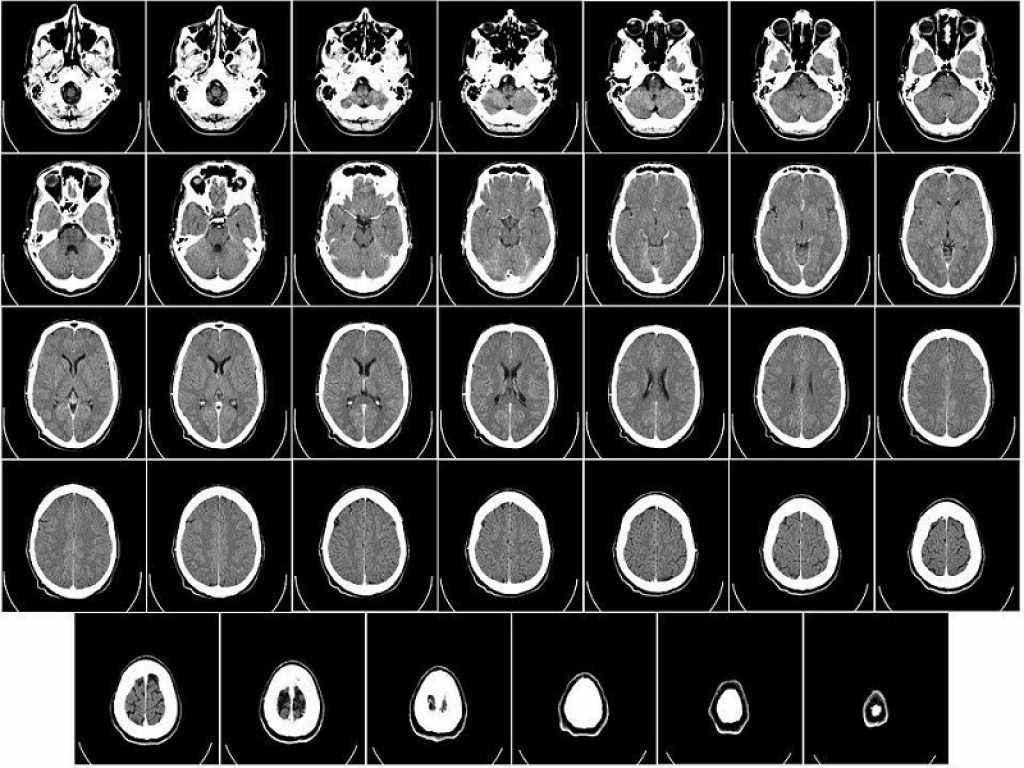

La Malattia di Alzheimer è la prima causa di demenza nella popolazione anziana. Generalmente, i sintomi progrediscono lentamente e peggiorano con il passare del tempo, diventando talmente gravi da interferire con le attività quotidiane. La diagnosi, anche in fase precoce, viene oggi effettuata grazie ad esami sul liquido cerebro-spinale e con la PET, esami che però sono costosi o invasivi, ed il cui utilizzo non è a disposizione di tutte le strutture ospedaliere. Per questo i ricercatori sono da tempo impegnati a scoprire dei ‘marcatori periferici’, ovvero delle molecole che possono essere identificate con un semplice prelievo di sangue. Lo stesso concetto vale per altre demenze non-Alzheimer, fra cui la demenza frontotemporale. Al di là della diversa patogenesi delle demenze, è importante sottolineare che i processi patologici che avvengono nel cervello iniziano 10-15 anni prima dello sviluppo della demenza conclamata. Sarebbe dunque necessario uno screening nel tempo della popolazione a rischio, nell’ottica di selezionare precocemente (ai primi sintomi, o addirittura in assenza di sintomi) quali persone dovrebbero essere sottoposte ad ulteriori approfondimenti.